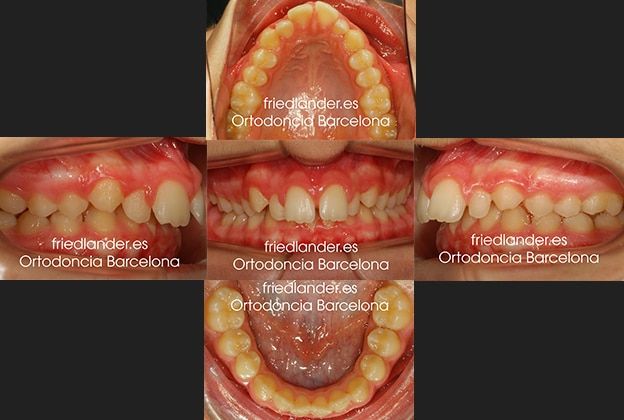

Caso 28 Tratamiento con aparato de Herbst y brackets de autoligado (Clase II severa)

Tras la exploración clínica de la paciente observamos una clase II severa (mandíbula retruída) con arcadas dentales estrechas con los dientes posteriores inclinados hacia lingual (hacia adentro) presenta un incisivos lateral microdóntico (incisivo lateral pequeño). En la exploración del perfil de la paciente observamos un mentón retruído. Explicamos a la paciente que el problema está en la mandíbula y no en el maxilar superior.

Los resultados oclusales después de 20 meses de tratamiento: